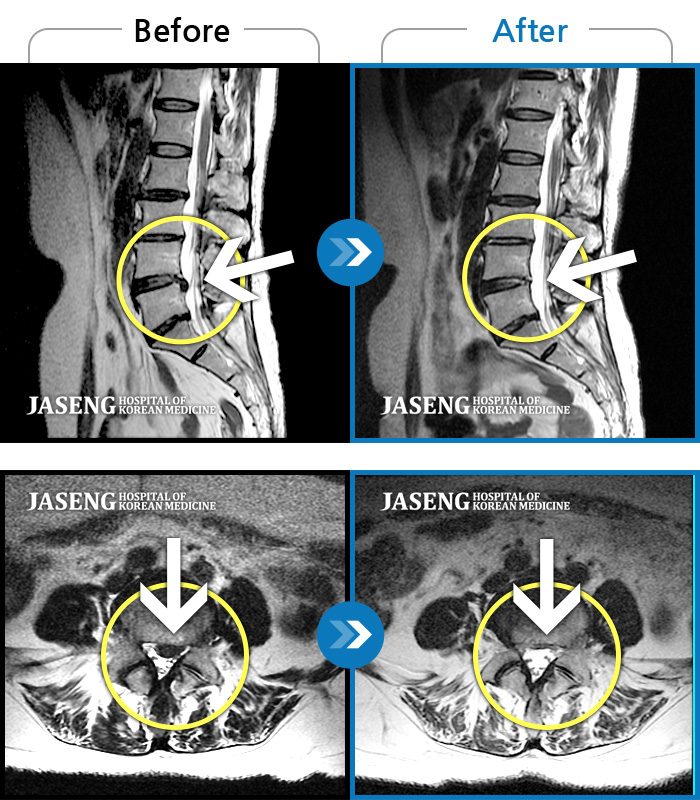

제가 가지고 간 MRI 영상자료를 보시면서 수술하지 않고도 충분히 고칠수 있다는 희망적인 말과 증상에 대해 자세히 설명해주시고 앞으로 어떻게 치료할 것인지에 대하여 알기쉽게 설명해주셔서 감사했습니다.